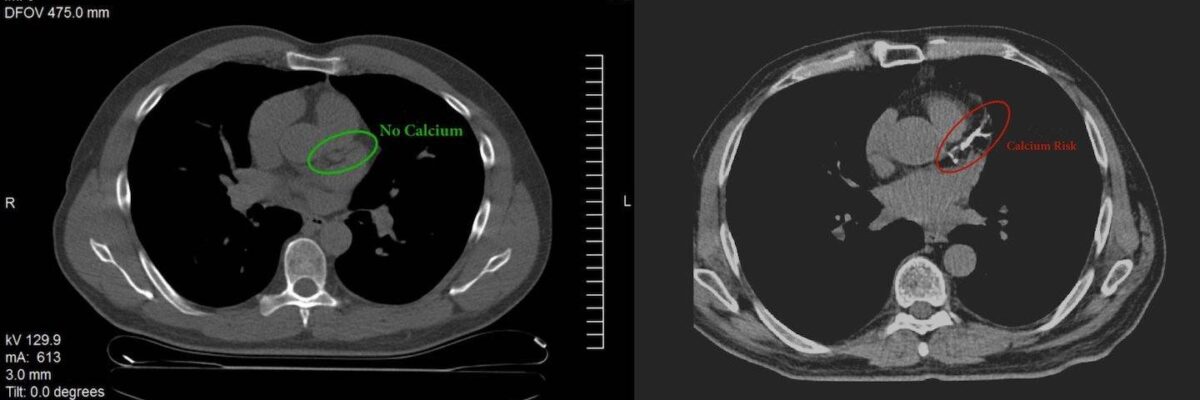

I’ve heard a number of people quoting the 10-year risk of an event for someone with a CAC score of zero is about 0.4%, or 4 cases per 1,000 individuals. Basically, the thinking goes, if you see no calcium on the CAC, there is little to no risk of CVD over the next decade, so there is no need to treat, even if the biomarkers are, well, for shit. I have always rejected this logic for reasons too long for a Sunday morning casual email, but I do want to point out a few things.

Second, if you look at the paper I allude to at the top (CAC and fitness), the rates seem even higher. Consider table 2: People with a CAC of 0 (i.e., ZERO) had a 0.9% (CI: 0.6% to 1.3%) “hard event” (i.e., heart attack, stroke, death) rate. This was calculated from the following raw data: 3,729 people had a score of 0, and over the follow-up period of 8.2 years, 27 hard events occurred. This is much higher than people like to quote in the camp of “if your CAC is zero you can ignore your lipids.” Caveat emptor.